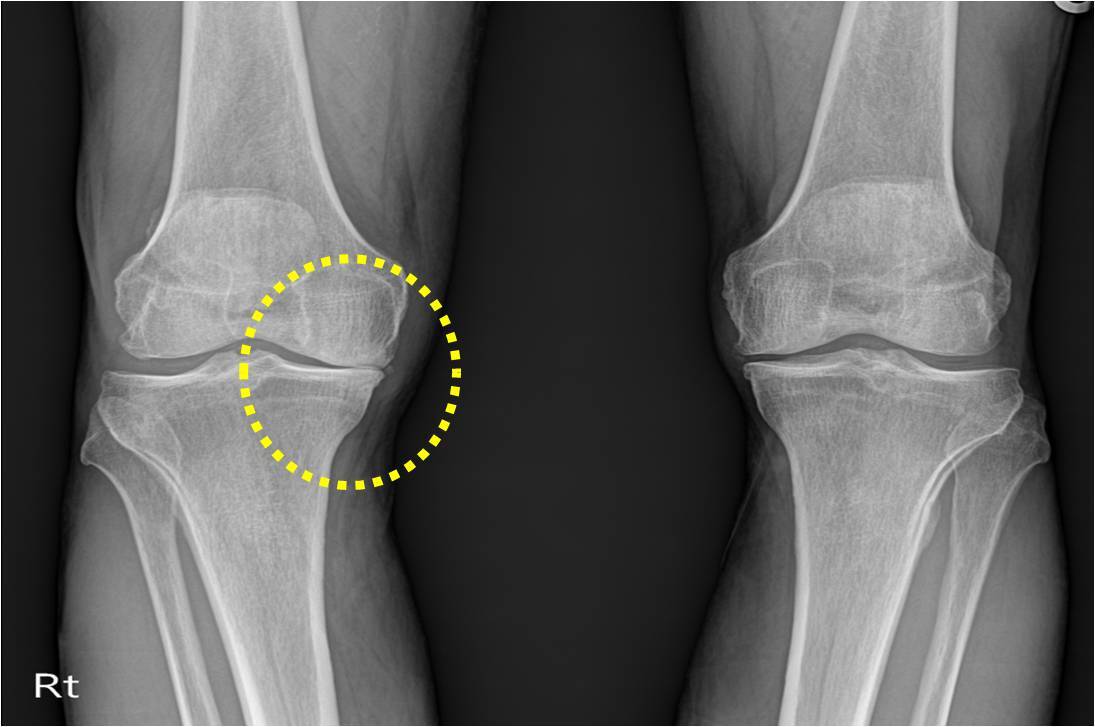

태행성 관절염과 류마티스 관절염은 모두 관절에 발생하는 질환이지만, 다음과 같은 차이점이 있습니다.

태행성 관절염과 류마티스 관절염 차이

- 퇴행성 관절염: 관절의 노화로 인해 연골이 마모되거나 손상되어 발생합니다.

- 퇴행성 관절염: 주로 무릎, 어깨, 고관절 등 큰 관절에서 발생하며, 관절의 통증과 부종, 관절의 변형 등이 나타납니다.